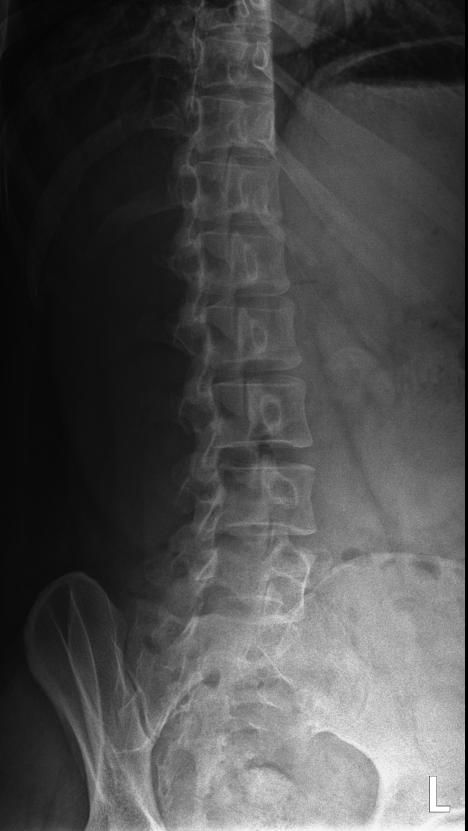

척추분리증인가요??(엑스레이 있어요)

한 병원에서는 척추분리증이라고 하고 한 병원에서는 척추분리증이 아니라고 해서요. 혹시 아래 사진에서 척추분리증 소견이 보이는 사진이 있나요??

여기까지가 a병원에서 찍은 사진이고 아래가 b병원에서 찍은 사진이에요!

• 4번 째 사진

B병원 사진에서는 비교적 흐리게 보이지만 잘 보면 B병원 엑스레이에서도 같은 부위에 분리증을 확인할 수 있습니다.

두 사진을 비교해서 보았을 때 큰 문제가 있어 보이지는 않으며 엑스레이상 척추분리증 진단이 어렵거나 애매한 경우에는 추가적인 검사 MRI를 통해 진단을 받아보시는 것도 방법이라고 생각합니다.

제가볼때 엑스레이상에 분리증은 보이지않지만 각도에따라 그리고 기계에따라서 달라질수있으니 정확하게 하고싶다면 MRI검사를 추천합니다 감사합니다~